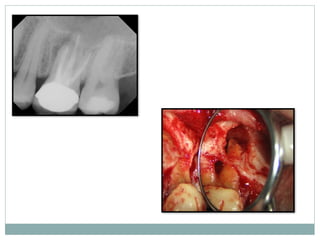

Root resection

Hemisection

Root resection

A root resection or amputation is done when

one of a tooth's damaged roots is removed while

keeping the healthy root or roots in place.

Indicated in :-

multirooted teeth with grade II to IV furcation

involvements

Hemisection

 It is splitting of a two-rooted tooth into two separate

portions

 This process has been called bicuspidization or

separation as it changes the molar into two

separate roots.

 It is most likely to be performed on mandibular

molars with buccal and lingual class II or III

furcation involvements